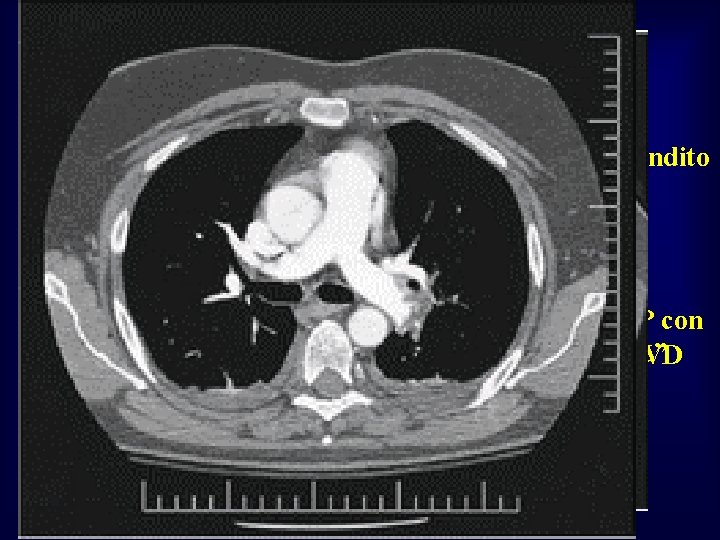

• • donna di 29 anni A) prima della trombolisi: VD ingrandito e • sintomi: ipocinetico dispnea ingravescente TAC polmonare: • B) dopo alteplase: EP con trombosi “a cavaliere” normalizzazione del VD